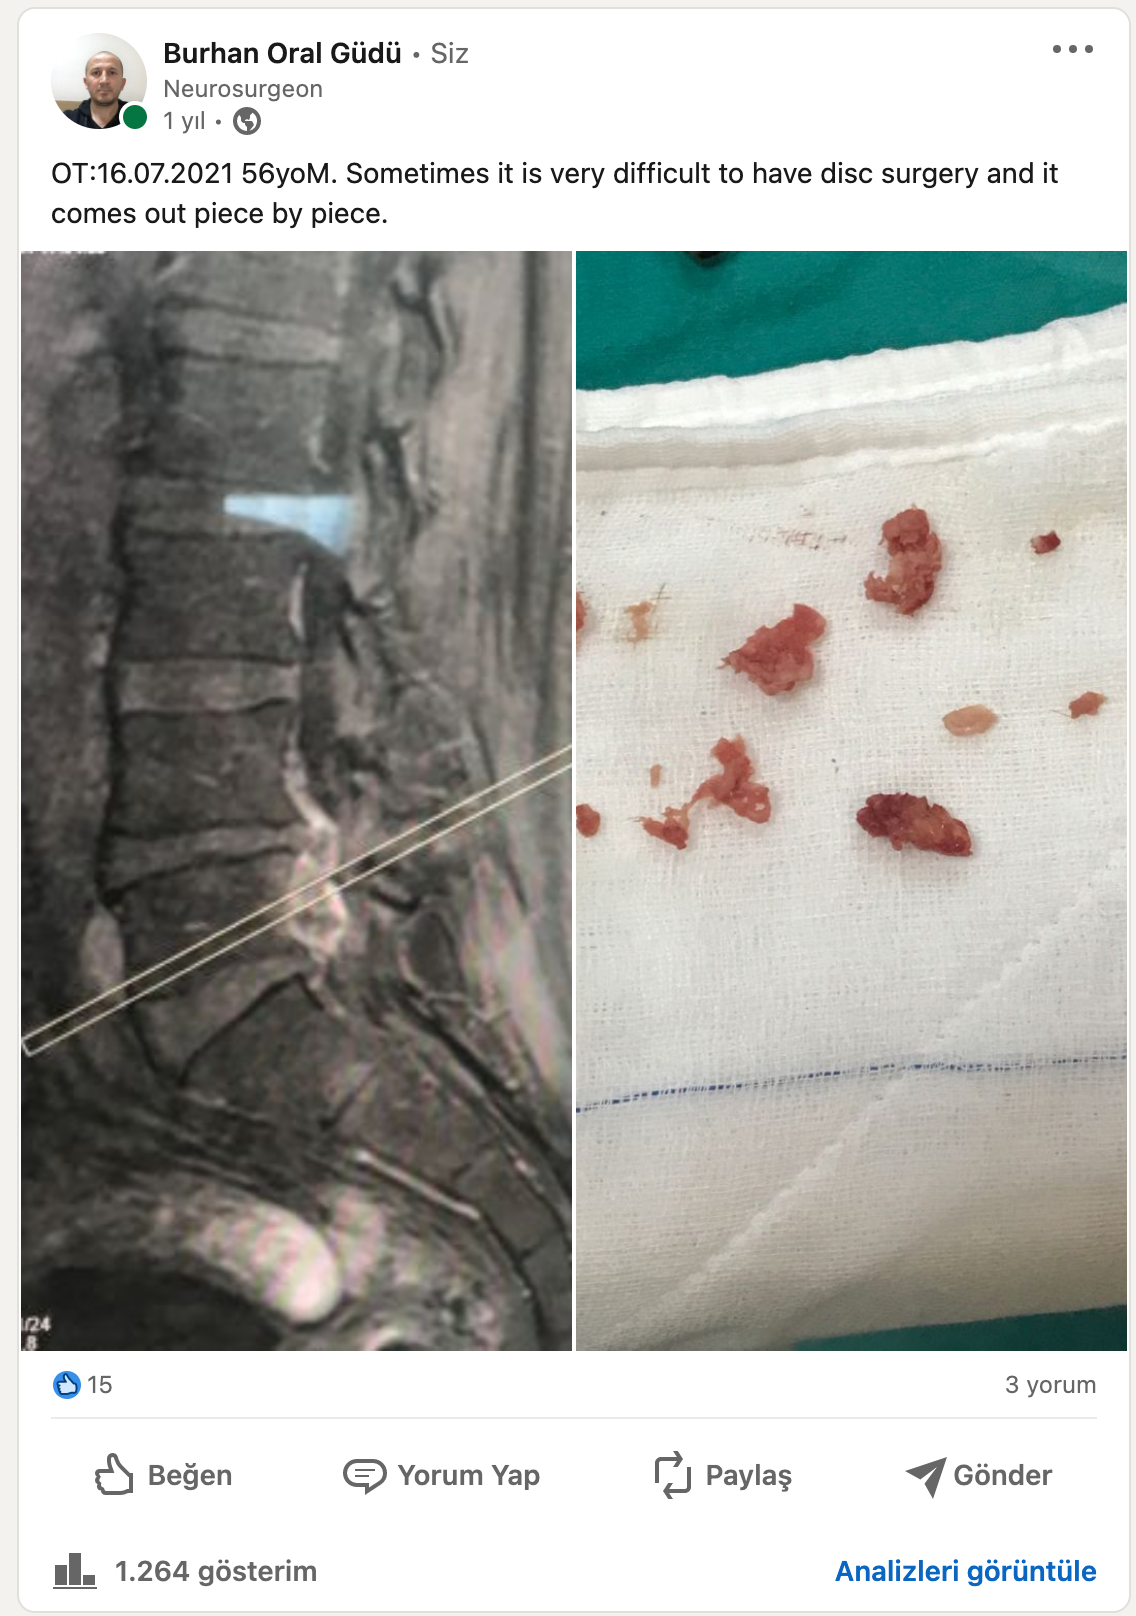

Bel fıtığı bilgi

Siyatik